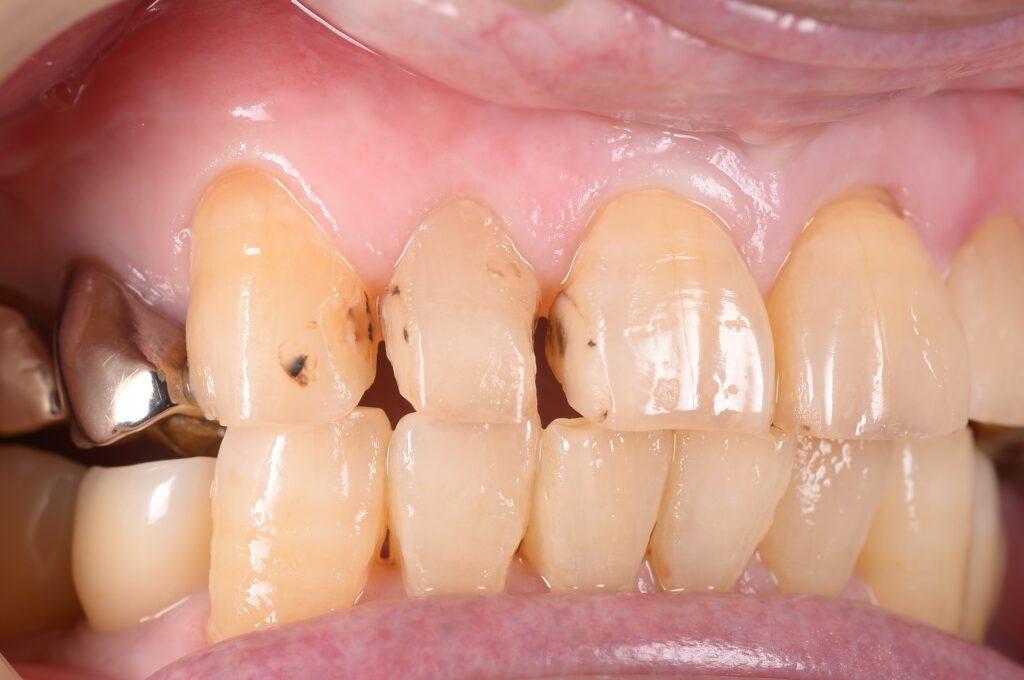

【27歳女性】7ヶ月で前歯の歯並びが改善✨マウスピース矯正(iGO)で手に入れた理想の笑顔

こんにちは!しんデンタルクリニックです🍀 心地よい春風が吹く季節になりましたが、皆様いかがお過ごしでしょうか。今回は「前歯の歯並びが気…more